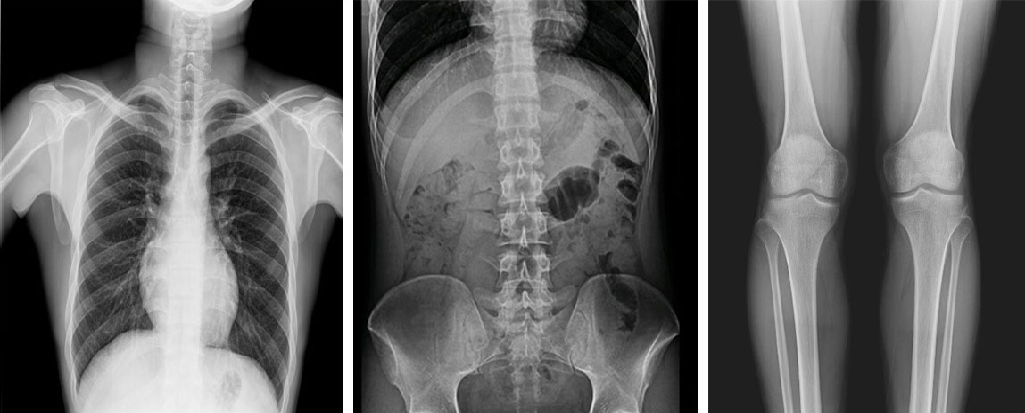

在功能上,動(dòng)態(tài)DR已不再局限于簡(jiǎn)單的拍片功能,而是集數(shù)字化攝影、數(shù)字化透視、數(shù)字化造影、數(shù)字化實(shí)時(shí)點(diǎn)片于一體,臨床用途廣泛,可應(yīng)用于臨床各科室,如體檢科、內(nèi)科、外科、骨科、創(chuàng)傷科、急診科等。

PLD8000系列數(shù)字透視攝影系統(tǒng)集數(shù)字化攝影、數(shù)字化透視、數(shù)字化造影、可視化點(diǎn)片等多種功能于一體,搭載高品質(zhì)高壓發(fā)生器、球管與平板探測(cè)器,確保性能穩(wěn)定的同時(shí)成就高清成像,同時(shí)提高機(jī)架自動(dòng)化程度,并且配備智能化電動(dòng)床體,帶來智能化、人性化操作體驗(yàn),全面滿足各級(jí)醫(yī)療機(jī)構(gòu)放射檢查需求。